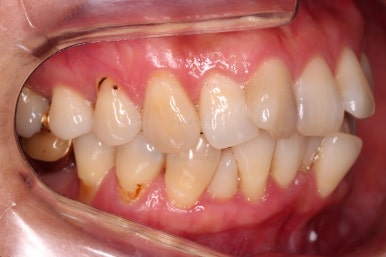

동래임플란트교정 초진 시 입안의 모습입니다.

치열이 전반적으로 삐뚤어져 있는 양상이고요.

아랫니가 윗니보다 더 많이 삐뚤어 있는데요.

임플란트가 이미 있을 경우

임플란트는 교정이 되지 않습니다.

뼈에 단단히 붙어 있기 때문에 힘을 줘도 원하는 위치로 이동되지 않습니다.

이번 환자분의 경우 임플란트가 어금니 크기보다 작게 제작이 되어 있어서 추후에 교합을 맞추기도 곤란한 상황이었어요.

그래서 교정 후에 임플란트 뿌리 부분은 그대로 사용하고 머리 부분만 재제작 하기로 했습니다.